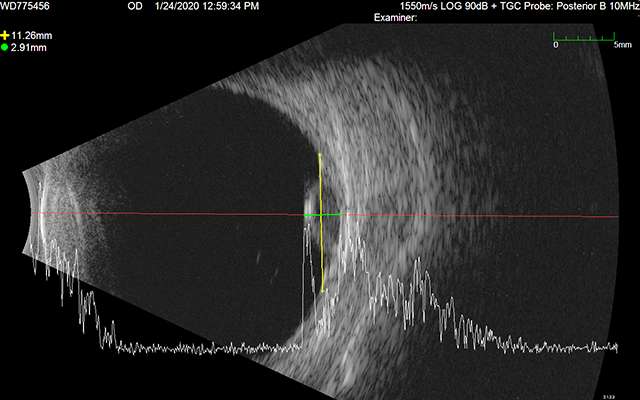

Ultrasound Images

A pair of ultrasound b-scans are used to determine the elevation of the tumor. Ideally, these images should illustrate cross-sections of the longest dimension of the tumor, and a plane perpendicular to that longest dimension. Radial and circumferential cross-sections are also acceptable. Eye tumors are often not clearly visible in CT (or MR) imaging alone. Ultrasound b-scans provided the most accurate measurements and cross-sections of ocular tumors for treatment planning purposes.

US1

US2